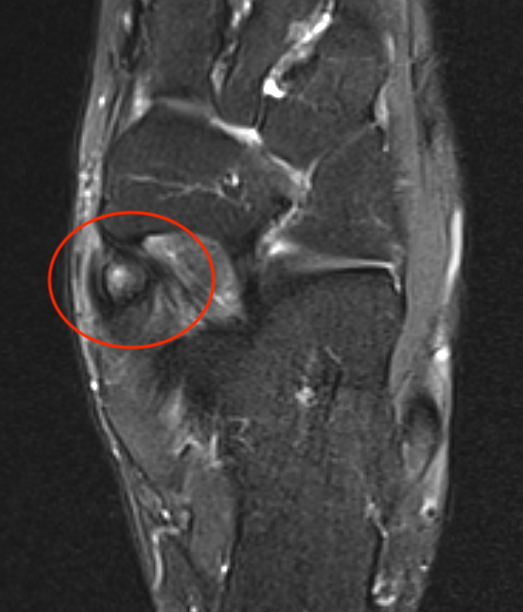

MRI

Show edema about a symptomatic accessory navicular